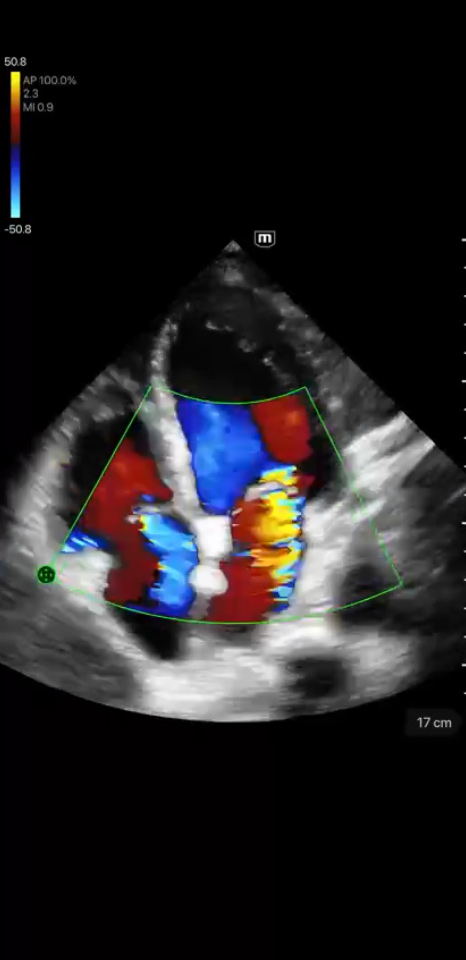

Clinical Images

Mitral and Tricuspid Regurgitation

Clinical Images

Mitral and Tricuspid Regurgitation